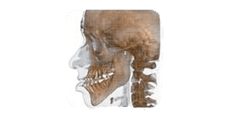

Radiografia specifica per la bocca

Lo studio si avvale di specifiche strumentazioni per assicurarti un’accurata analisi ortodontica. In primis, lo staff medico si affida all’alta tecnologia del sistema Cone Beam NewTon 5G XLUno, fondamentale per settori medici quali implantologia, endodonzia, chirurgia orale e ortodonzia, in grado di creare immagini 3D capaci di mostrare patologie potenziali e anomalie strutturali con una precisione senza precedenti; dall’altra si sottolinea la presenza della tecnologia SafeBeam™, il sistema più sicuro sia per i pazienti che per lo staff medico. Grazie a questo strumento, gli esperti eliminano qualsiasi possibilità di esposizioni radioattive, mantenendo un contrasto dell’immagine nitido e definito, a prescindere dalle dimensioni anatomiche o dalla densità ossea osservata.